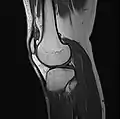

MRI

Both anterior cruciate ligament (ACL) and posterior cruciate ligaments (PCL) are hypointense on both T1 and T2 weighted images of MRI. However, some high signal striations are often seen at the distal part of the ACL, making ACL higher intensity than PCL on MRI scans.[17]

Knee MRI (PD TSE FS sagittal)

Knee MRI (T1 TSE sagittal)- Knee MRI (sagittal TSE FS)